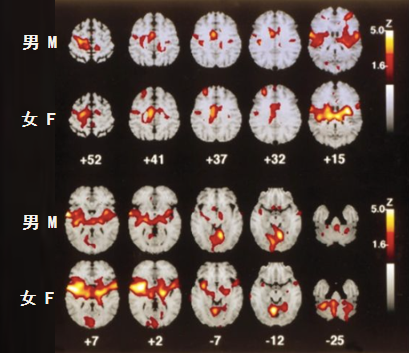

2002年曾有科学家实验过“男女对疼痛产生的不同敏感度”,即在同样50°C的热觉刺激源下,观察男女生的大脑的反应。结果发现,女生参与痛觉感知的对侧岛叶和丘脑激活程度更活跃,表明女生“疼痛”反应会比男生更强烈!

图源:中华麻醉学杂志2004年第4期